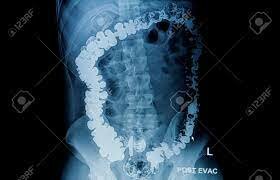

• 1997 - Uso de Bario

1997 - Uso de Bario

Utilizado como contraste para estudios